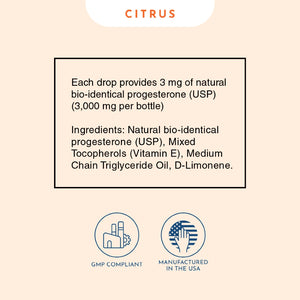

Our bio-identical progesterone is designed and formulated like no other. Unlike progesterone creams that are typically low concentration or contain thyroid suppressive oils, or progesterone pills / tablets that are largely inactivated by your liver, or suppositories that are prone to crystallization and can’t be absorbed… Progesterone Oil solves all of these problems. It’s highly concentrated at more than 10% progesterone, doesn’t crystalize, and contains a special solution allowing for close to 100% absorption. The secret lies in the special formulation with Vitamin E, which acts as a carrier to deliver the progesterone directly into the bloodstream. This makes it the quickest and most absorbable bio-identical progesterone source available.

Our Progesterone Oil contains 1 fl. oz. / 30 ml (over 3,000 mg per bottle) of pure, bio-identical progesterone, with high-quality Vitamin E, and pure non-GMO MCT oil (Coconut oil).